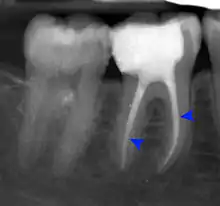

Pressure or pain in the jaw area can be associated with dilaceration. Checking in with a general dentist and an endodontist should be done if a patient feels these symptoms.[4] Signs in radiographic imaging will indicate an bend in the tooth's root as opposed to a straight growth.[1] Dilaceration of the crown, the top part of the teeth that we see when we smile, can be visually seen for diagnosis. Crown dilaceration will present itself as a tooth that is angled to face outward or inward. It will be a non axial displacement and more of a longitudinal displacement.[5]

Dilaceration can be diagnosed with a simple radiograph of the affected teeth. However, if the bends are more lingual or facially present,[1] more advance imaging techniques may be necessary. In some cases a cone-bean CT scan may be useful to create a three dimensional view.[9]